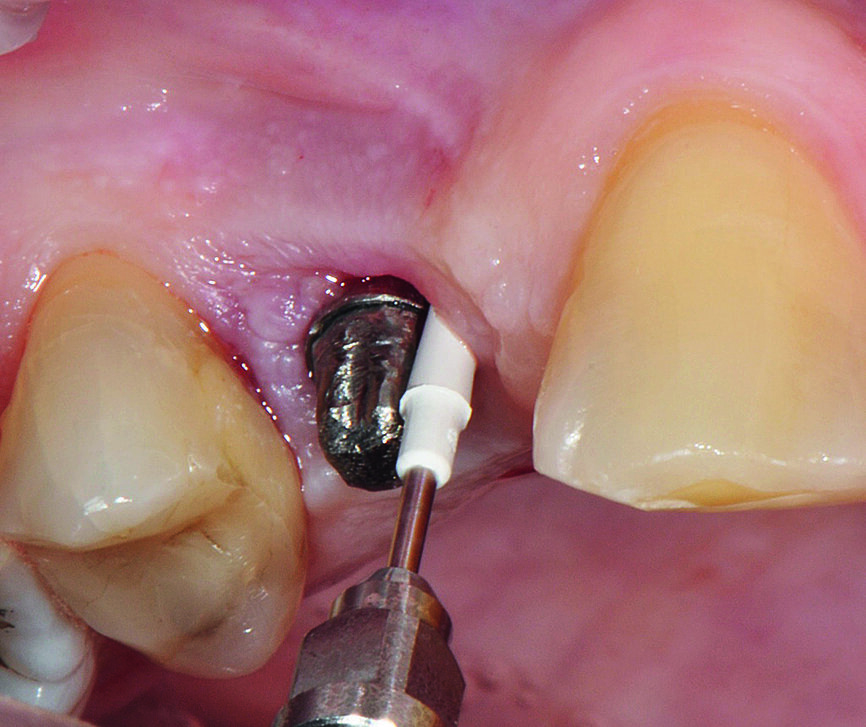

Fig b : Implant en position 14 affecté par une péri-implantite : sondage péri-implantaire après retrait de la couronne prothétique.

Fig. 3 : Excès de ciment autour de l‘implant